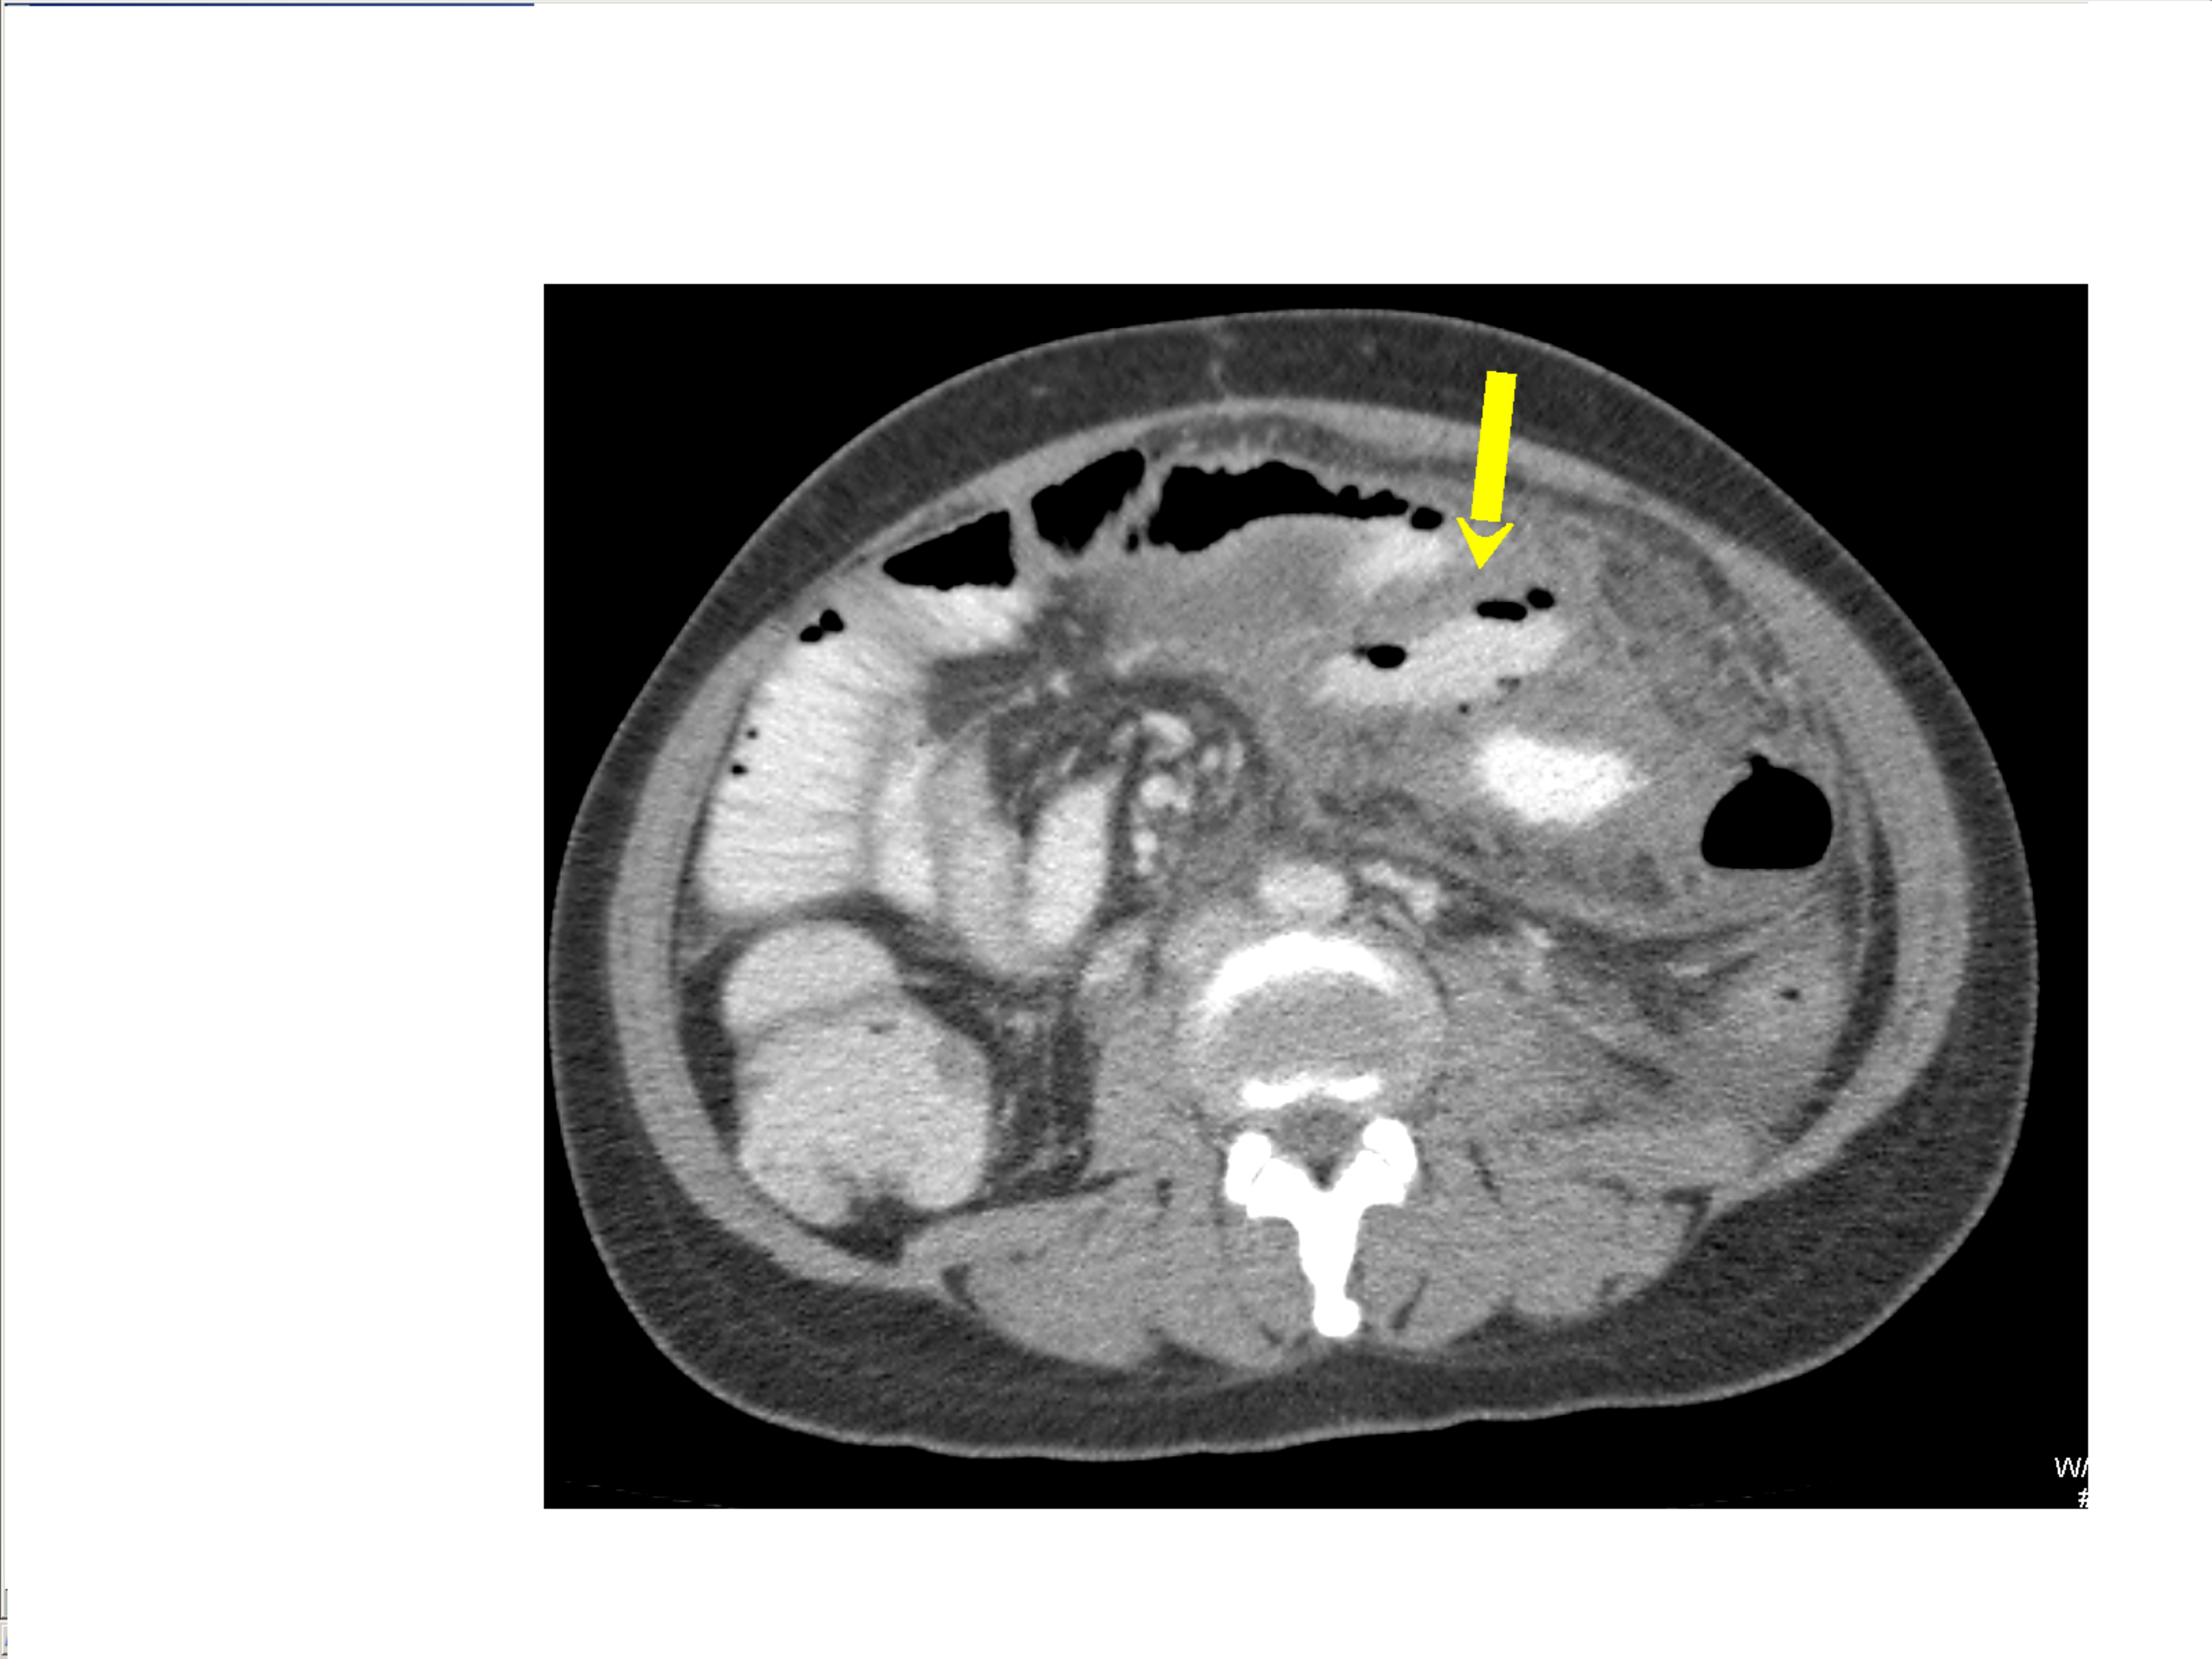

Small bowel obstruction is a common clinical presentation that presents a diagnostic conundrum. Over the last 2 decades, there has been a paradigm shift in the radiological investigation of small bowel obstruction (SBO) and in the indication for and timing of surgical intervention. Cross sectional imaging (predominantly computed tomography) has largely replaced the widespread use of radiographic small bowel follow-through studies as the imaging modality of choice for SBO. This article illustrates the current imaging modalities available for diagnosis of small bowel obstruction. (Full text available online at www.medpharm.tandfonline.com/ojfp) S Afr Fam Pract 2015; DOI: /10.1080/20786190.2014.977052